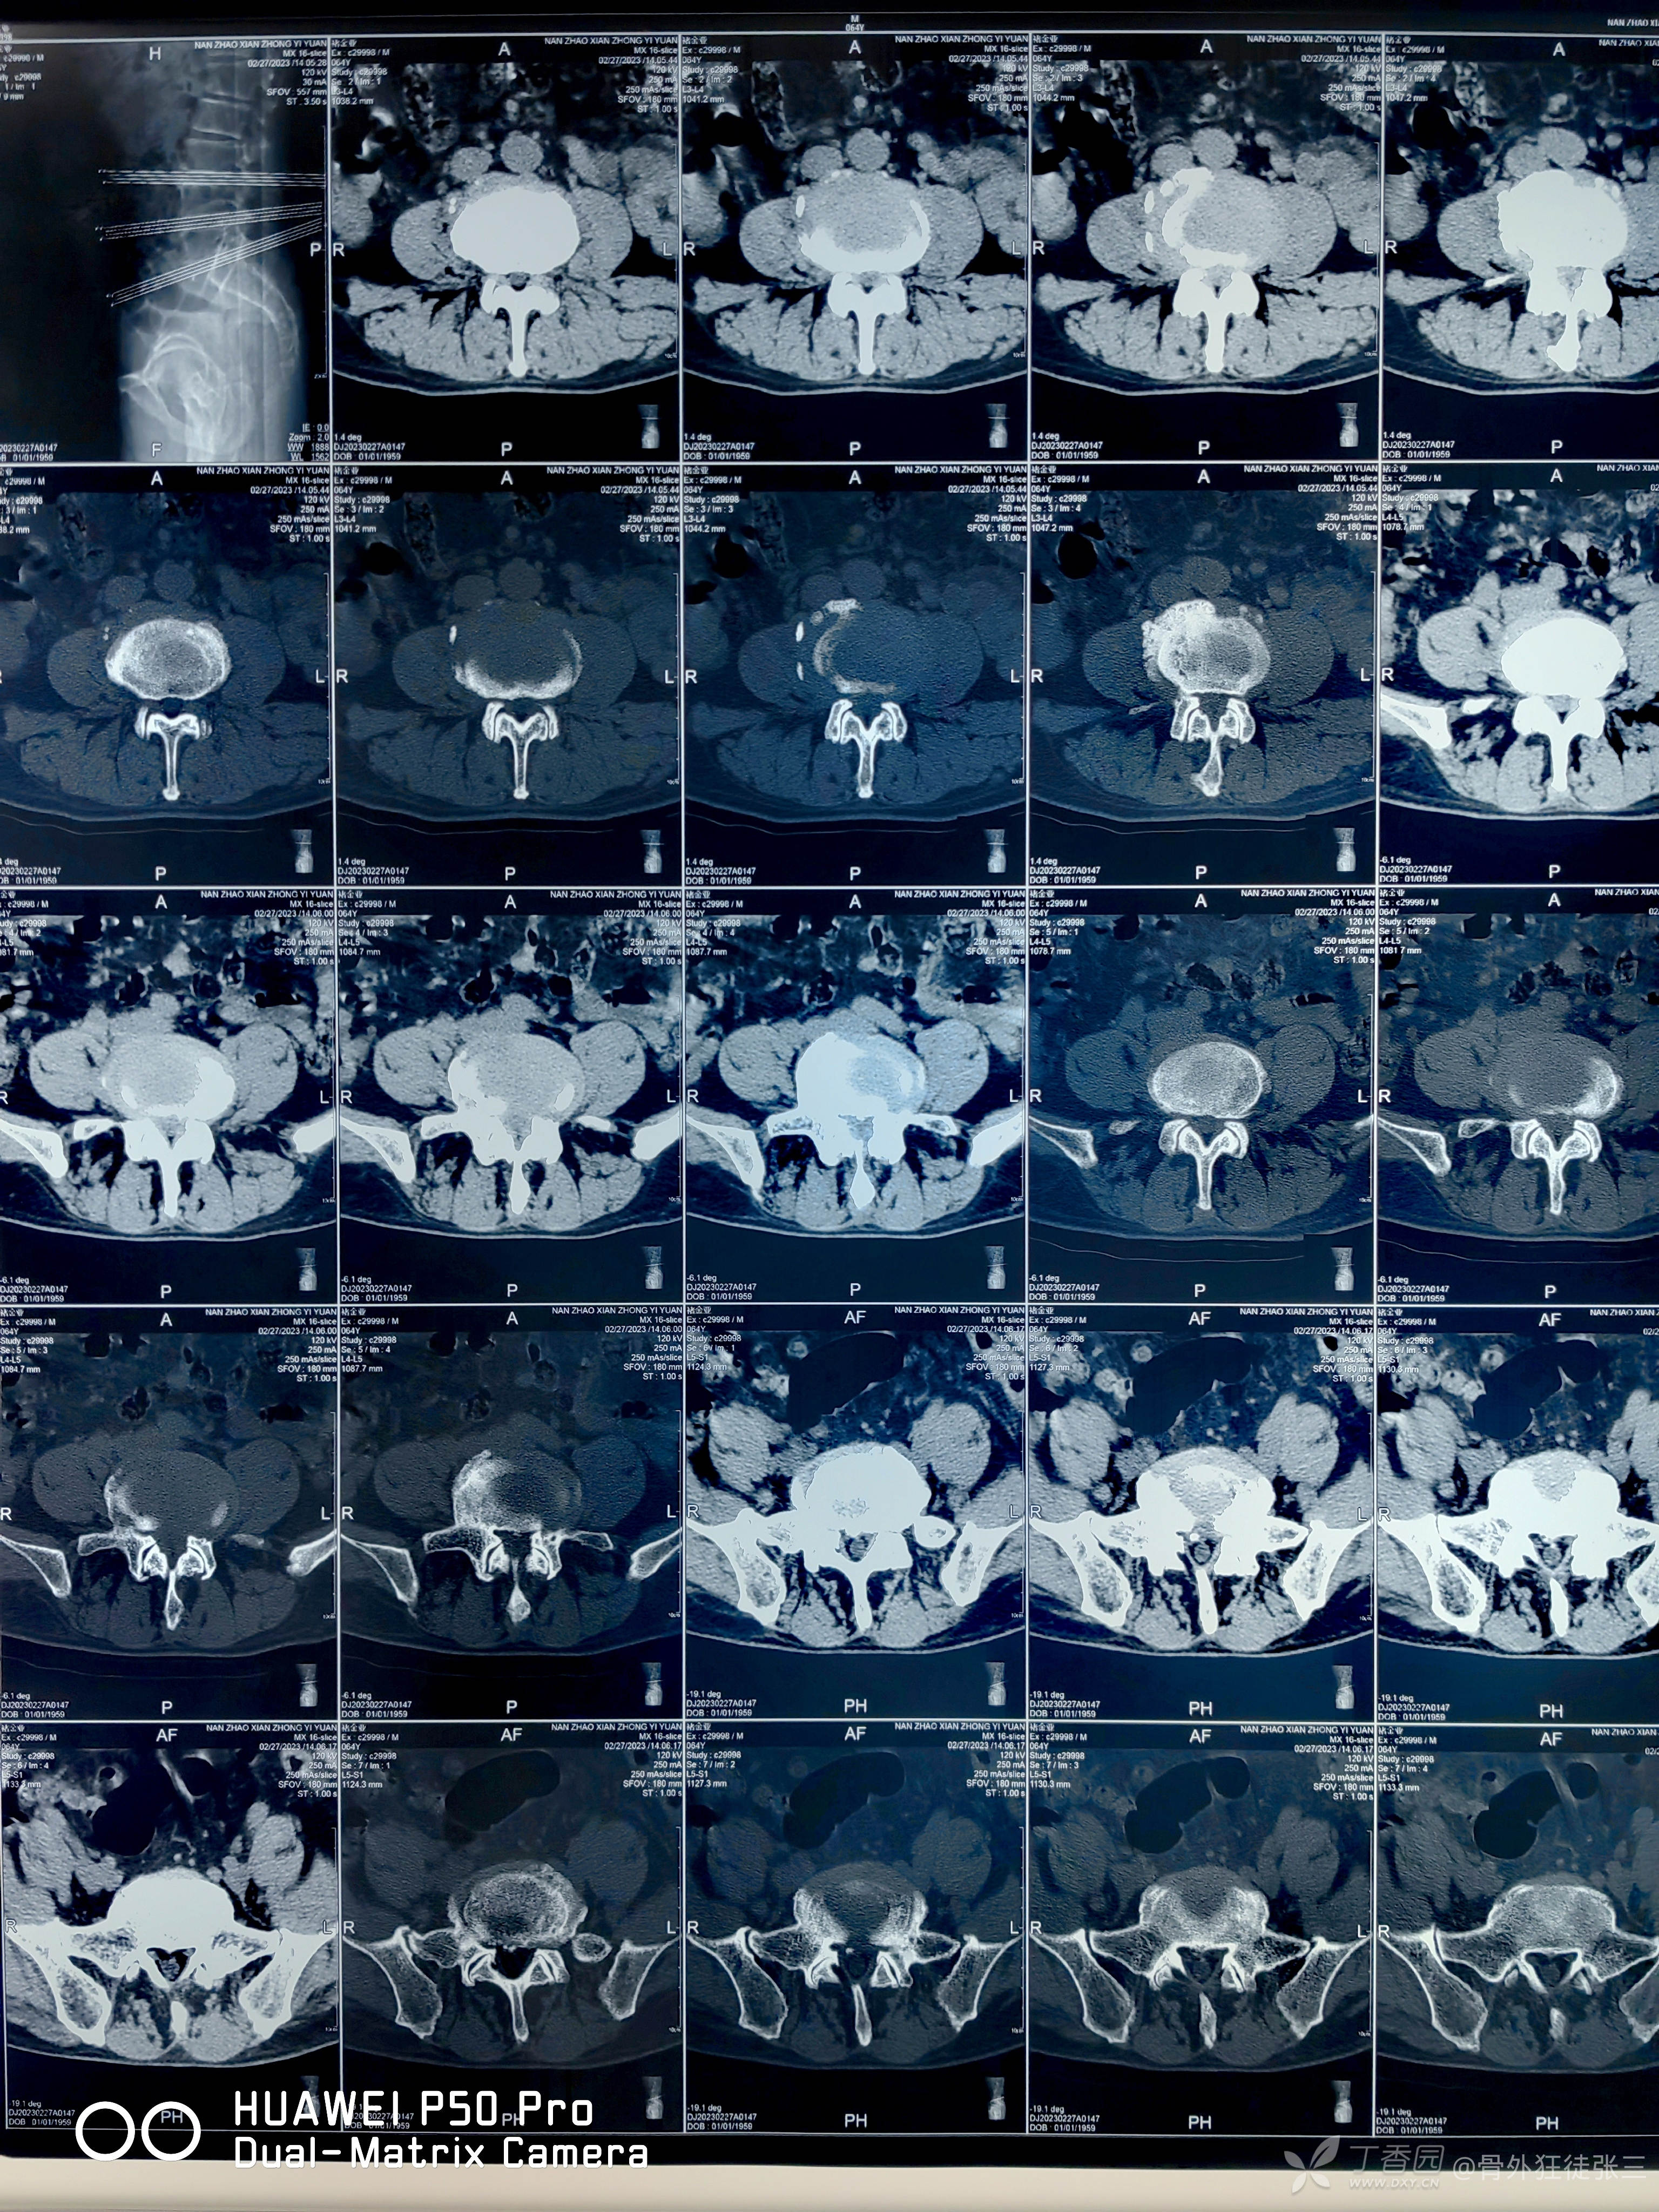

辅助检查:

发育性腰椎管狭窄:这种椎管狭窄是由先天性发育异常所致。

包括营养、外伤等原因造成的先天性椎管狭窄。

大部分人开始可能不出现任何症状,但到中年以后,由于脊柱的一些老化或损伤,会有椎管狭窄症的症状及体征出现。